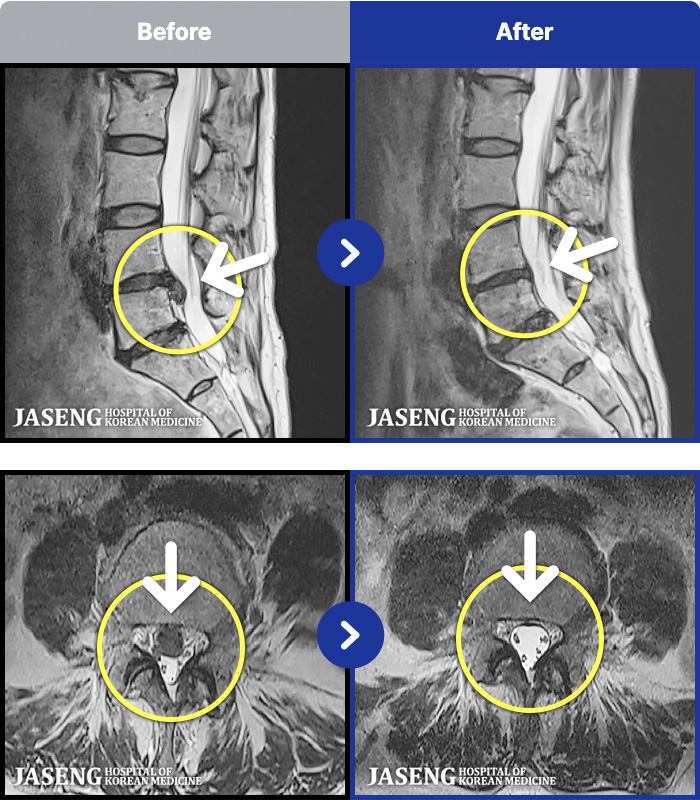

1,297 MRI ũ ʸ Ȯϼ.

MRI ġ

㸮 , ٸ

ǿ

ȯ

㸮ũ

¥

2019.11.08

[] 19.01.22~19.07.16

ȯںп Ǹ ǿ ԿǾ, ο ġ ۿ Ƿ ġḦ Ͻñ ٶϴ.